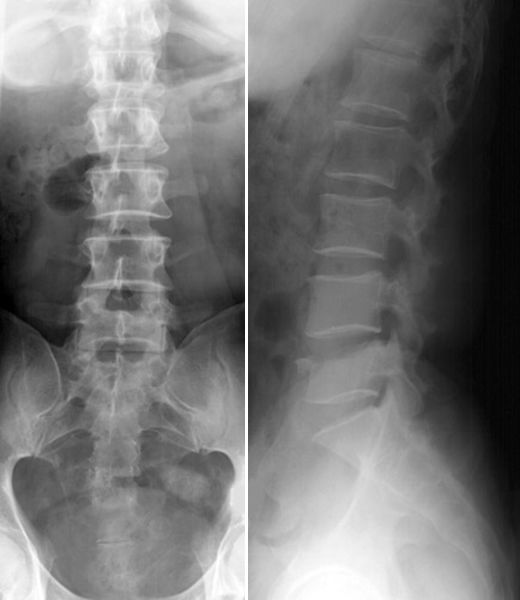

正常腰椎

L5腰椎骨折